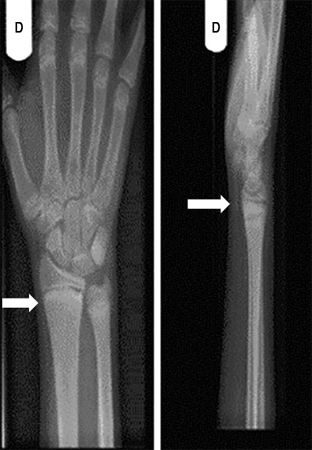

Uma radiografia de um osso longo revelando escavação, afunilamento e desgaste da metáfise é necessária para o diagnóstico. O alargamento da placa epifisária e a perda de definição da zona de calcificação provisória na interface epífise/metáfise são os primeiros sinais de raquitismo.

A ulna distal é o local que melhor demonstra os sinais precoces da mineralização prejudicada, e as metáfises acima e abaixo dos joelhos são os locais mais úteis em crianças mais velhas.[4][Figure caption and citation for the preceding image starts]: Punho direito de um paciente com raquitismo por deficiência de vitamina D antes do tratamento. Sua radiografia do punho direito revelou placas finais escleróticas e aumentadas do rádio e ulna (setas)Seerat I, Greenberg M. Hypocalcaemic fit in an adolescent boy with undiagnosed rickets. BMJ Case Reports 2010; doi:10.1136/bcr.10.1136/bcr10.2008.1153 [Citation ends].

[Figure caption and citation for the preceding image starts]: Punho direito de um paciente com raquitismo por deficiência de vitamina D depois do tratamento (setas)Seerat I, Greenberg M. Hypocalcaemic fit in an adolescent boy with undiagnosed rickets. BMJ Case Reports 2010; doi:10.1136/bcr.10.1136/bcr10.2008.1153 [Citation ends].